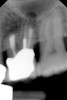

Fig 4. Preoperative radiograph showing aggressive external root resorption and thin dentinal walls.

Figure 4

Clinical procedure: Regeneration of the endodontic pulp space is indicated for cases with very thin dentinal walls and an open apex that is more than 1 mm in diameter radiographically (Figure 4). Disinfection of the root canal system is performed using sodium hypochlorite irrigation followed by a triple antibiotic paste dressing that is left in place for 1 week. At the second visit, ethylenediaminetetraacetic acid (EDTA) is used to condition the dentin walls, which results in the release of growth factors, and bleeding is stimulated in the periapical tissues (where stem cells are located), with the aim of filling the pulp space with a stable blood clot, which would serve as the scaffold. MTA is then placed at the canal orifice in contact with the clot to protect it from coronal microleakage (Figure 5 and Figure 6). In time, the clot should be replaced with a reparative tissue of variable composition, and the root walls should continue to thicken due to the deposition of a dentin-like material on the pre-existing root dentin27,28 (Figure 7 and Figure 8).